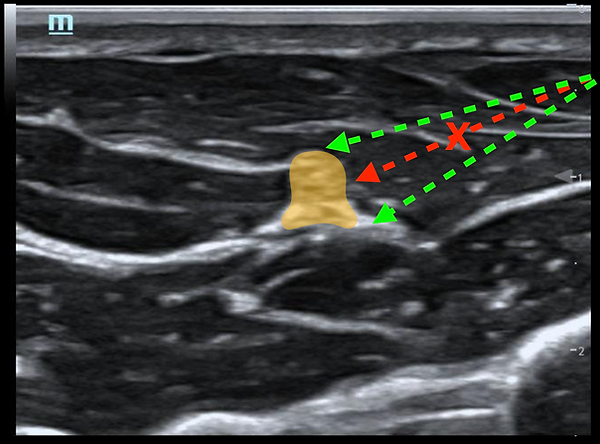

C'est simple, ne JAMAIS viser un nerf avec une aiguille. Toujours viser à ce que votre trajectoire passe à côté du nerf.

Évitera de percer le nerf si le patient fait un mouvement subit OU si vous perdez momentanément la visualisation de votre aiguille.

Votre objectif est d'amener votre aiguille au coin nerf-fascia et d'y débuter votre hydrodissection!